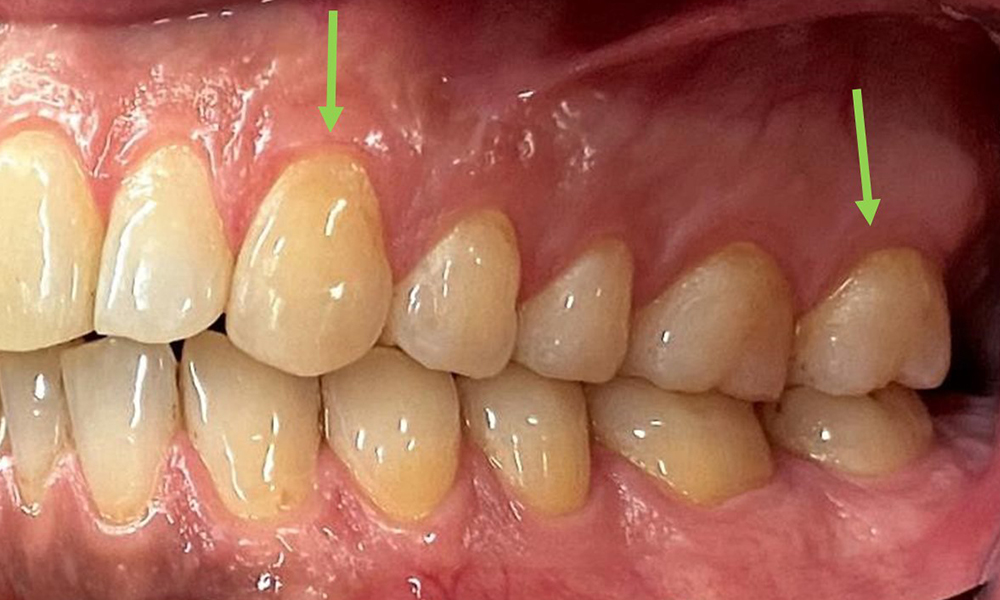

There were no pathological extraoral findings. During intraoral examination, inspection of the frontal view revealed brownish discolouration near the keratinised gingiva and at the transition to the moveable mucosa (Fig. 2), which could be attributed to nicotine consumption. Whitish mucosal lesions were observed on the palate, particularly near the maxillary molar palatal surfaces, indicating increased keratinisation and can also be attributed to nicotine consumption. The tongue was covered with a removable white and brownish coating.

At 1 to 3 mm, the clinical probing depths were within the physiological range. Maxillary recessions of up to 1 mm were observed from 13 to 16 and 23 to 27. The BOP was 15%.

The arrows indicate plaque accumulations in the cervical region

Fig. 8: The arrows indicate plaque accumulations in the cervical region, © Dr R. Krapf